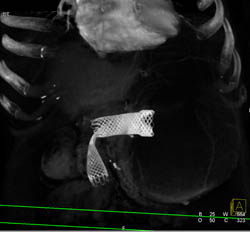

Perforated Gastric Tumor- Gist With Stent